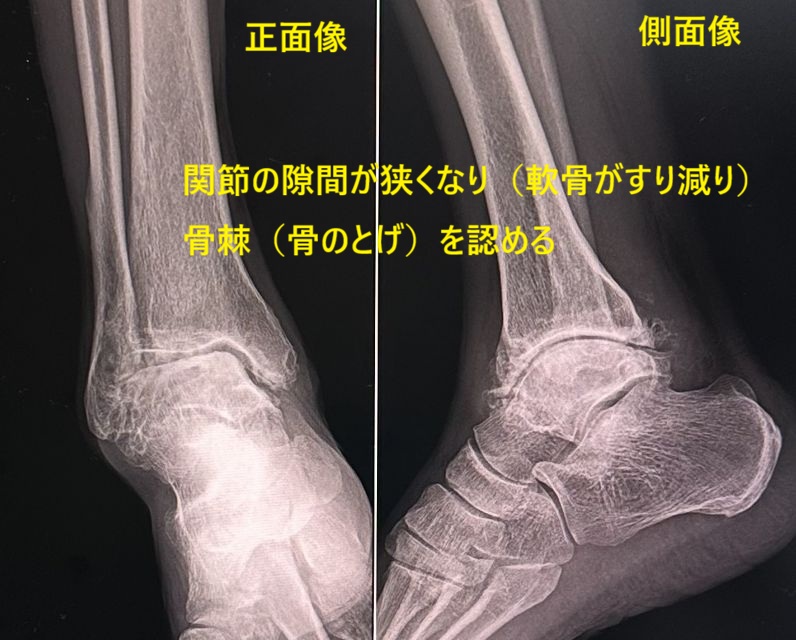

| 変形性関節症は、関節軟骨の老化や磨耗によって起こる軟骨と骨の進行性の変性疾患です。人間は二足歩行ですから、体重がかかる荷重関節(膝関節、股関節、脊椎、足関節)は体重がかからない非荷重関節(肩関節、肘関節、手関節)に比べ変形性関節症の発生を多く認めます。 しかし、荷重関節の中にあって足関節は股関節や膝関節に比べ変形性関節症の頻度は少ないようです。このことは足関節が形態的に安定した関節で、多数の強靭な靭帯を有し、支持性や安定性に関与する足根骨があるため足関節にかかる衝撃や負担が少ないためと考えられています。 変形性足関節症 変形性足関節症は、一次性(明らかな原因がない症例)と二次性(明らかに原因がある症例)に分かれます。二次性は下腿骨折や足関節果部骨折、足関節靭帯損傷、踵骨骨折などの外傷や感染、炎症性疾患後に発生します。大半は二次性です。中には麻痺性疾患(脳性麻痺やポリオなど)や先天性内反足に伴って発生することもあります。 症状・診断 症状は痛みや腫れ、変形、運動障害、歩行障害です。診断はレントゲン検査では関節裂隙の狭小化(軟骨が磨耗している)や骨棘形成(骨のとげ)、不安定性(関節がグラグラしている)などの所見を認めます。詳細な情報にはMRIやCTが必要です。 治療 1)保存的治療 日常生活動作の注意点や肥満に対する指導を行います。疼痛緩和に物理療法やアセトアミノフェン、炎症緩和に非ステロイド性抗炎症剤、外皮用薬などを処方します。効果がなければトラマドール、デュロキセチンを検討します。難治例にはステロイド注射を試みます。 運動療法として股のストレッチングや膝のストレッチング、足首のストレッチング、アキレス腱のストレッチング、股の筋力強化、膝の筋力強化、足首の筋力強化、アキレス腱の筋力強化を指示します。不安定性を認める症例では足底板や短下肢装具の着用をすすめます。 2)手術的治療 保存的治療で改善されなければ手術を検討します。術式は靭帯再建術や骨切り術(内反・外反変形矯正術)、人工足関節置換術、関節固定術などが行われます。近年、人工足関節置換術の成績は向上しているようです。変形足関節症は、将来ロコモや要介護へと進展しますので要注意です。